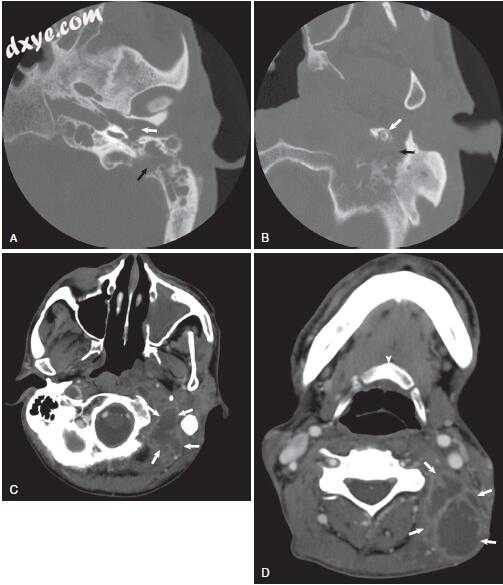

图-1. 颞骨骨扫描计算机断层扫描显示乳突的浑浊与保留骨隔。 注意皮质骨(白色箭头)和耳后肿胀和液体收集(黑色箭头)的缺陷。

图-2. 轴向(A)和冠状(B)颞骨计算机断层扫描显示乳突浑浊,伴有骨隔缺失。 注意皮质骨和耳后液采集中的缺陷(箭头)。

图-3. 颞骨骨扫描计算机断层扫描显示中耳(白色箭头)和乳突(黑色箭头)的混浊。